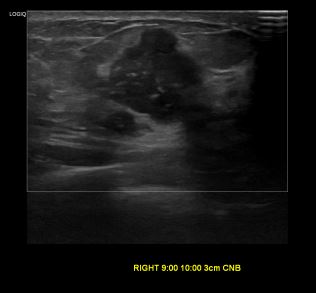

상기환자 우측 유방에 만져지는 멍울있어 내원하신 50대 여성분으로

우측유방 혹 총조직검사 시행해 유방암 진단되었습니다.